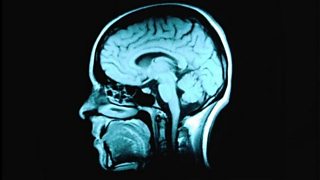

Susan Short and Ed Jones discuss potential new treatments for brain tumours.